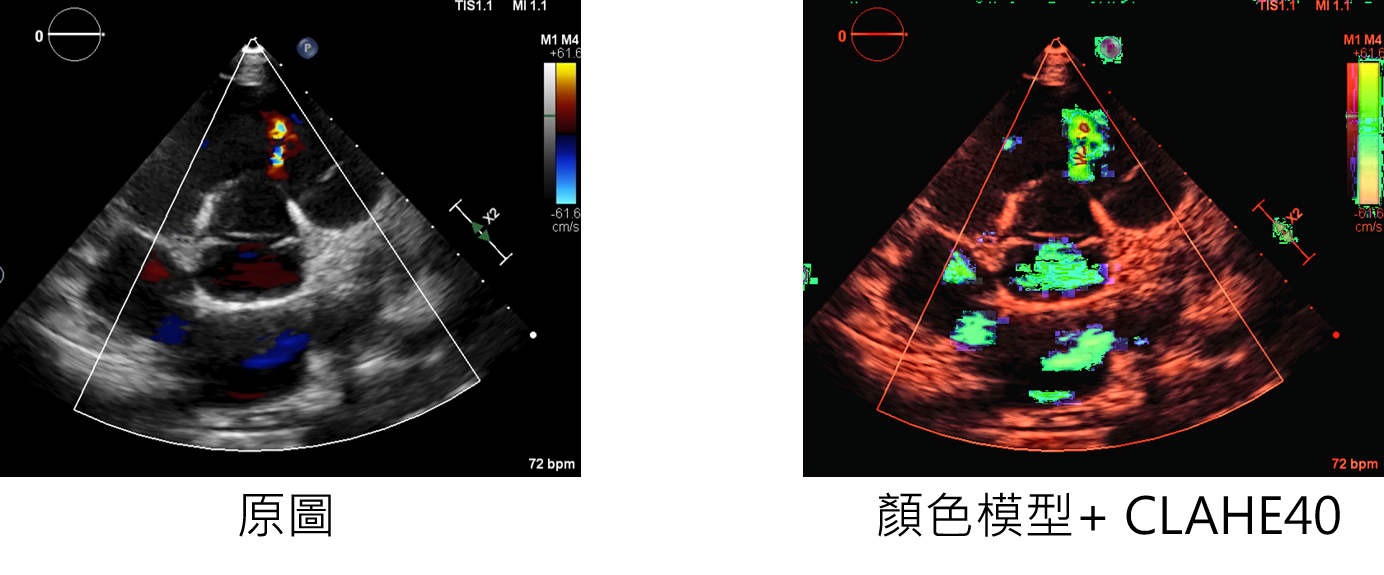

參數說明

CLAHEHSVcolor:增強方法

clahenum:設定每次處理的大小

輸入範例:

datagen=CustomDataGenerator(fun="CLAHEHSVcolor",clahenum=40,dtype=int)

*下圖為CLAHE-clahenum=40+HSV與原圖的對比